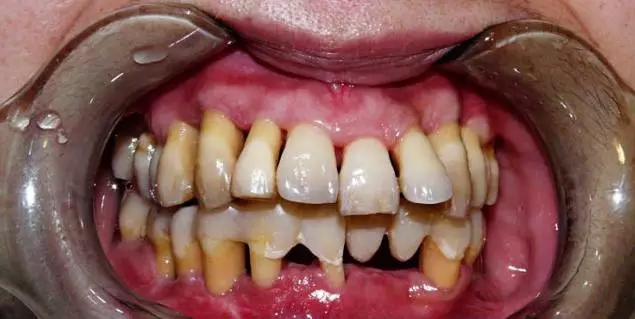

這個患者也是從千里之外來的,媽媽陪著她來,13顆牙齒是三度松動,其中有三顆牙齒下前牙牙槽骨吸收已經(jīng)到達(dá)根尖下方,這三顆就只能拔掉了;一顆左下六牙槽骨吸收也到了根尖,但是左側(cè)下后牙只剩下四、五、六三顆牙,如果拔掉六就只剩下四、五兩顆了,而且牙槽骨吸收也是接近根尖了,所以決定暫時保留左下六;11顆牙齒是二度松動,只有三顆牙齒是一度松動。這樣嚴(yán)重的牙周病,對我來說也是個非常大的考驗,講起女兒的病,媽媽哭得很可憐,我不忍心讓她們失望,只能盡力去幫助她保存牙齒,盡量少拔牙。

治療前頰側(cè):牙周紅腫、牙周溢膿,大量牙石

治療前腭側(cè):牙周紅腫、牙齦呈現(xiàn)暗紅色